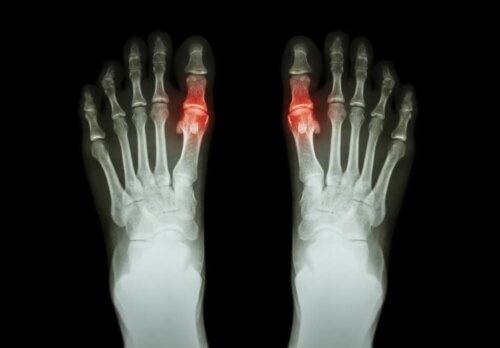

Leddgikt har en tendens til å vises i form av smerte og vanskeligheter med å bevege det berørte leddet eller leddene. Noen ganger innebærer det også stivhet og hevelse i samme område. Det kan påvirke bare ett ledd eller mange ledd samtidig. Det kan også være symmetrisk eller asymmetrisk.

Hver type har sine særegenheter, og tiden symptomene varer er varierende. For eksempel er revmatoid artritt en symmetrisk type leddgikt som påvirker små ledd, som fingrene. Urinsyregikt er derimot en type leddgikt som har en tendens til å påvirke bare et ledd.